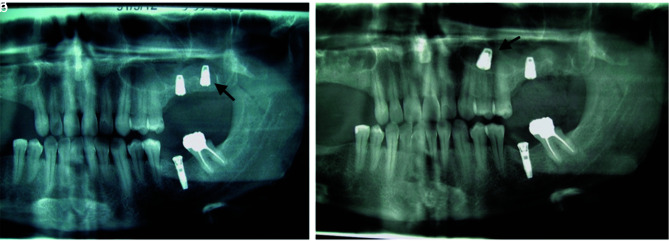

The use of dental implants to restore edentulous jaws has become commonplace. Usually, in the maxilla, following a tooth extraction, the height of alveolar bone decreases. This alteration in bone increases the risk of implants migrating into the sinus. In general, Caldwell-Luc and endoscopic surgery are performed to retrieve dental implants. In this case series, we collected data from 39 patients who had the complication of implant displacement within the maxillary sinus for 25 years. All the implants were removed using the Caldwell-Luc technique. Implant migration happened following functional loading, during the prosthetic procedure, due to lack of osseointegration in 3 patients, and during implant placement into the fresh socket in 3 patients. In the remaining cases, migration occurred preoperatively or postoperatively and prior to implant loading. Insufficient bone quantity is sometimes causing the implant to migrate to the maxillary sinus. In case of minimal bone height, a sinus lift before implant placement should be conducted. Retrieval of an implant pushed inside the maxillary antrum using the Caldwell Luc approach proved to be a reliable technique.